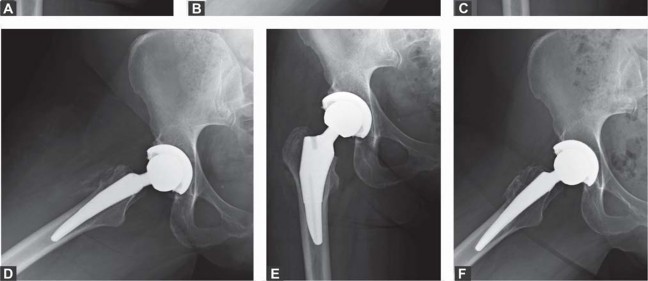

الزرعة نظام Taperloc Microplasty

يفضل الأستاذ الدكتور محمد هطيف استخدام نظام Taperloc® Microplasty من شركة Biomet (وارسو، إنديانا)، وهو أحد الخيارات المتاحة للزرعات الخالية من الأسمنت. يعتمد هذا النظام على تصميم إسفيني مخروطي وسطي-جانبي بدون ياقة، مصمم للتثبيت الذاتي والاستقرار الدوراني.

- المادة والتصميم: مصنوع من التيتانيوم (Ti-6AL-4V) ويتميز بطلاء مسامي رش بلازما محيطي قريب. تستخدم Biomet تقنية خاصة لتطبيق الطلاء المسامي بحيث لا يتم تسخين الزرعة بشكل كبير، مما يحافظ على مستويات عالية من مقاومة الإجهاد.

- الأحجام والتنوع: تتوفر السيقان في أحد عشر حجمًا، تتراوح أطوالها من 95 ملم إلى 130 ملم، وتزداد تدريجيًا جانبيًا بينما يظل الانحناء الأنسي ثابتًا. زاوية عنق-جذع 138 درجة، وهناك خياران للإزاحة: قياسي وجانبي.